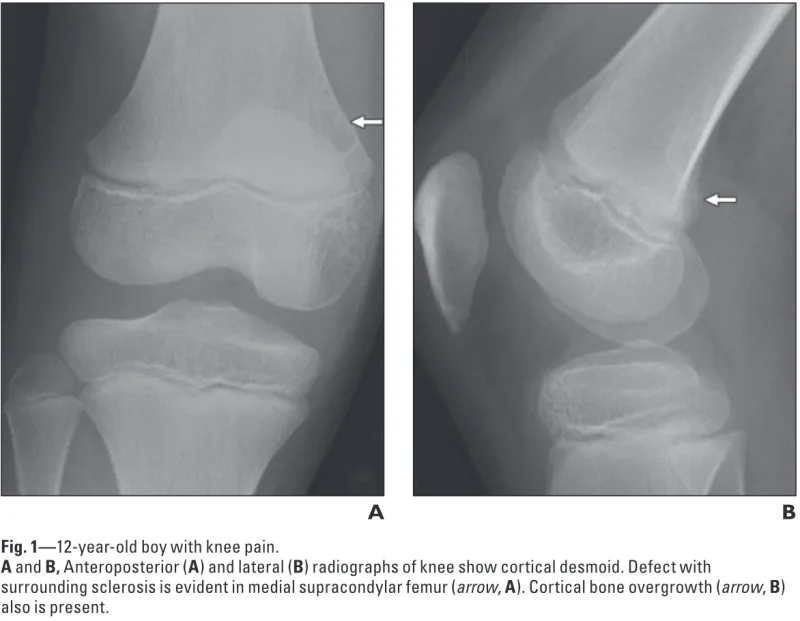

正面像(A)では, 大腿骨の内側部が透けるように写る病変が, 側面像(B)では, 骨が隆起するように写る病変がそれぞれ認められます.

引用元:Vieira RLR. MRI features of cortical desmoid in acute knee trauma. AJR Am J Roentgenol. 2011. 196.

X線写真を確認すると, 遠位大腿骨皮質骨不整 distal femoral cortical irregularity(以前は, 皮質デスモイドcortical dermoid, avulsive cortical irregularityなどと呼ばれていた)所見が疑われました.

遠位大腿骨皮質骨不整は, 小児期から青年期にかけて見られる, 骨腫瘍と誤認されやすい良性・一過性の病変です.

両側性のこともあり, 多くは無症状.

時間の経過とともに自然消失するため, 治療は不要です.